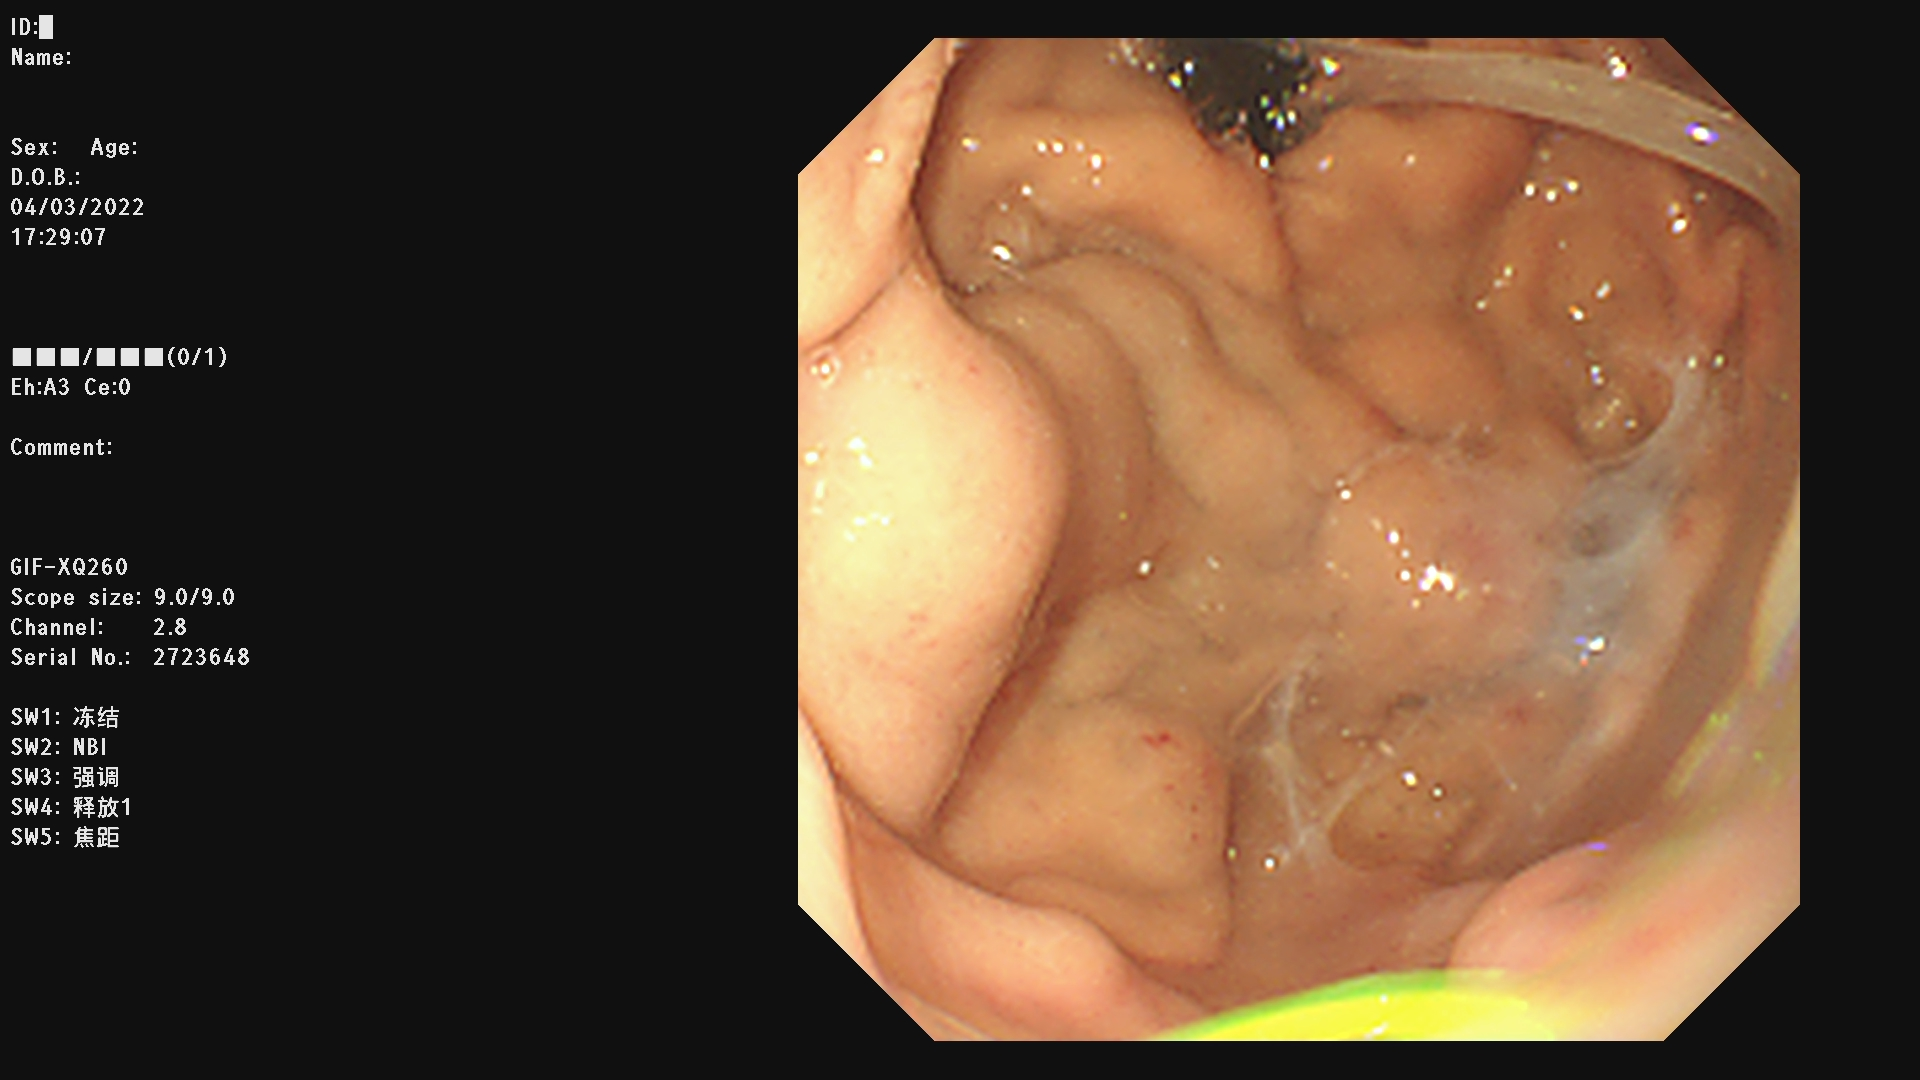

例一 :